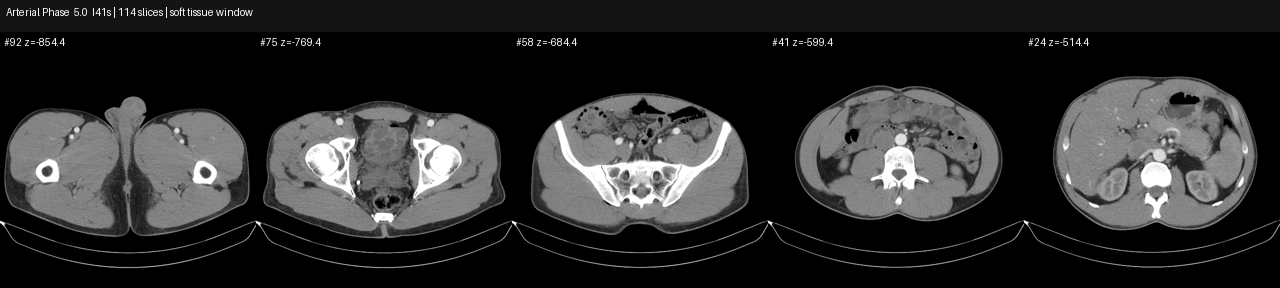

Arterial phase CT axial overview slices

arterial phase overview slices across pelvis and abdomen.